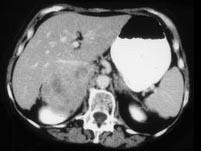

问题 女,37岁,向心性肥胖2个月,请结合所提供图像,作出诊断 ( )

选项 A、右肾上腺嗜铬细胞瘤 B、右肾上腺增生 C、右肾上腺腺癌 D、右肾上腺转移瘤 E、右肾上腺腺瘤

答案 C